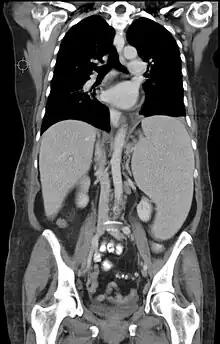

- Pruebas de imagen: es de elección la ecografía abdominal; aunque también se realizan TAC y gammagrafía.